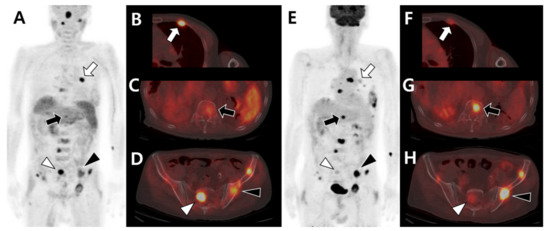

- Seo, H.J.; Choi, Y.J.; Kim, H.J.; Jeong, Y.H.; Cho, A.; Lee, J.H.; Yun, M.; Choi, H.J.; Lee, J.D.; Kang, W.J. Evaluation of Bone Metastasis from Hepatocellular Carcinoma Using (18)F-FDG PET/CT and (99m)Tc-HDP Bone Scintigraphy: Characteristics of Soft Tissue Formation. Nucl. Med. Mol. Imaging 2011, 45, 203–211. [Google Scholar] [CrossRef][Green Version]

- Ho, C.L.; Chen, S.; Cheng, T.K.; Leung, Y.L. PET/CT characteristics of isolated bone metastases in hepatocellular carcinoma. Radiology 2011, 258, 515–523. [Google Scholar] [CrossRef] [PubMed]

- Yoo, S.W.; Kim, D.Y.; Pyo, A.; Jeon, S.; Kim, J.; Kang, S.R.; Cho, S.G.; Lee, C.; Kim, G.J.; Song, H.C.; et al. Differences in diagnostic impact of dual-tracer PET/computed tomography according to the extrahepatic metastatic site in patients with hepatocellular carcinoma. Nucl. Med. Commun. 2021, 42, 685–693. [Google Scholar] [CrossRef] [PubMed]